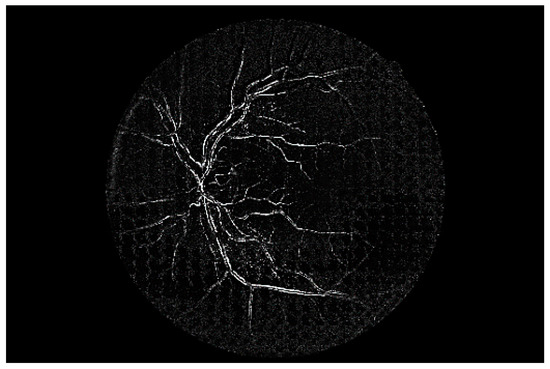

Figure 7 shows a simple example of the MLP method used in this study. The high-resolution fundus (HRF) [74] image dataset contains higher-quality retinal images compared to those of DRIVE, and provides both low- and high-quality retinal images. Figure 8 shows a low-quality retinal image. The bottom part of the image is unclear owing to white noise caused by environmental factors. Figure 9 shows a retinal vessel image created by performing vessel segmentation on Figure 8. The white noise seen in Figure 8 also affects vessel segmentation. Figure 10 is a high-quality retinal image and the white noise observed in Figure 8 has disappeared. The bottom part of the vessel stem is clearly visible, which did not appear in the original image. Figure 11 shows a retinal vessel image created by performing vessel segmentation on Figure 10. Unlike Figure 9, the bottom part of the vessel stem is shown clearly.

Figure 9. Retinal vessel image of Figure 8.